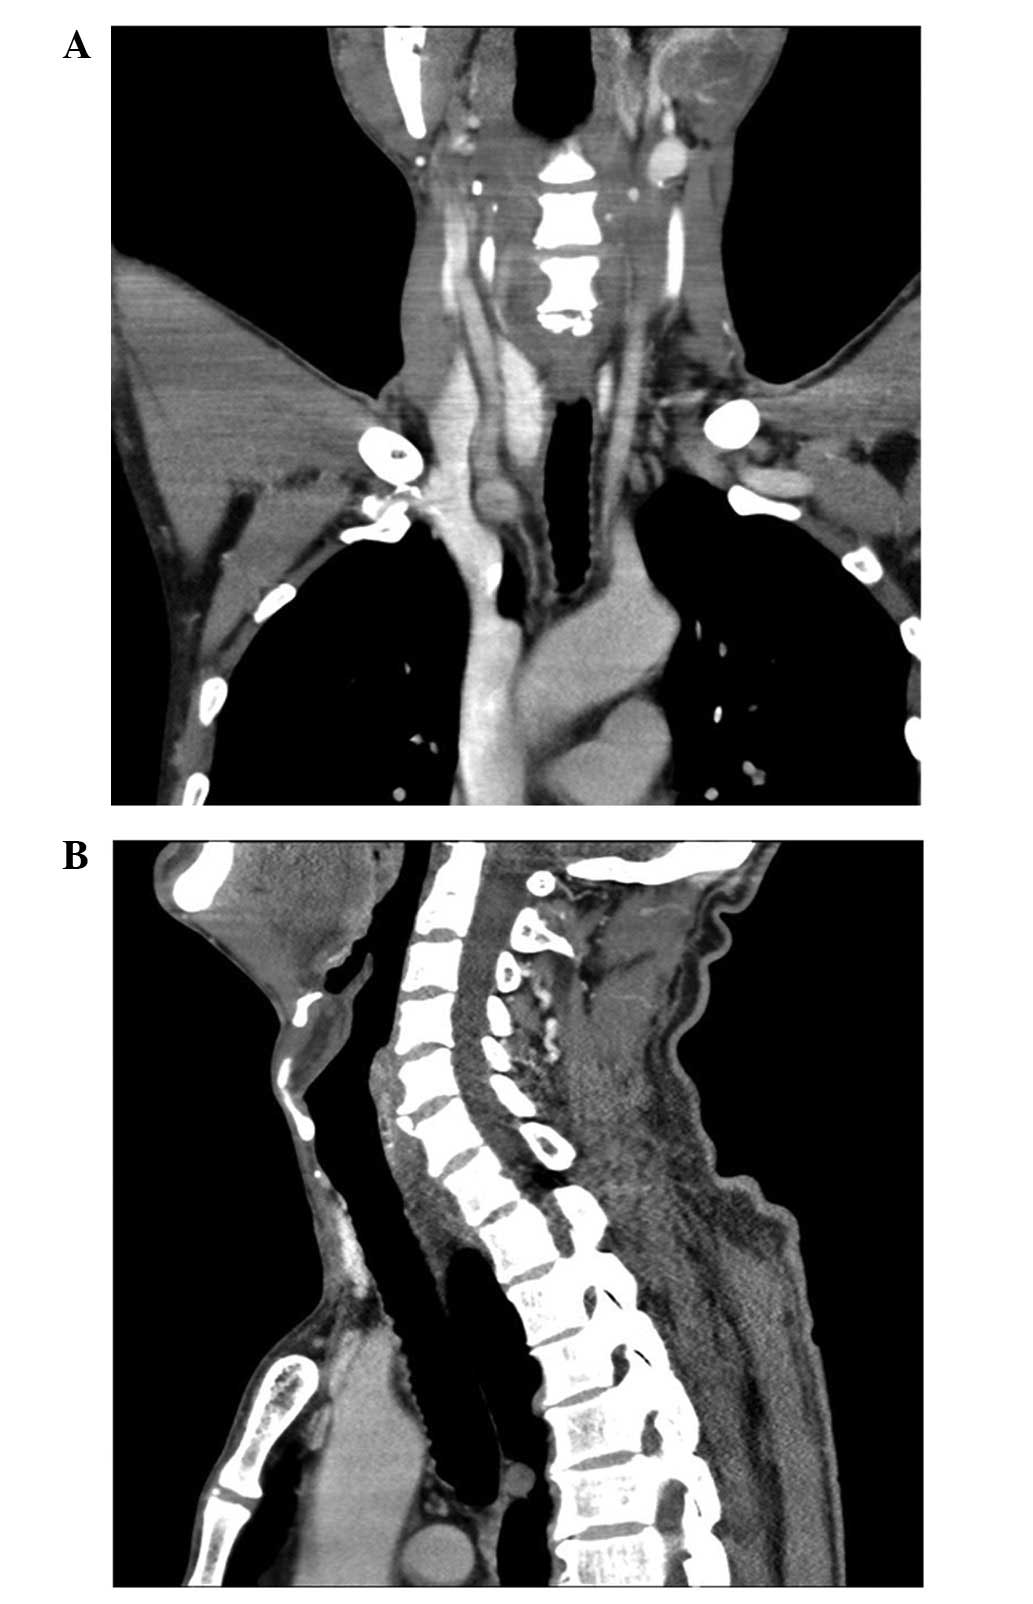

The patient underwent a right thyroid lobectomy and isthmectomy, with the excision of the cyst. The appearance of the giant PC was characterized by large cystic lesions with a thin wall and a watery fluid component (Fig. 3).

Figure 3.

Post-operative computed tomography scan showing that the giant parathyroid cyst had been removed, and that the displaced trachea and large vessels had returned to the normal positions. (A) Coronal scanning. (B) Sagittal scanning.